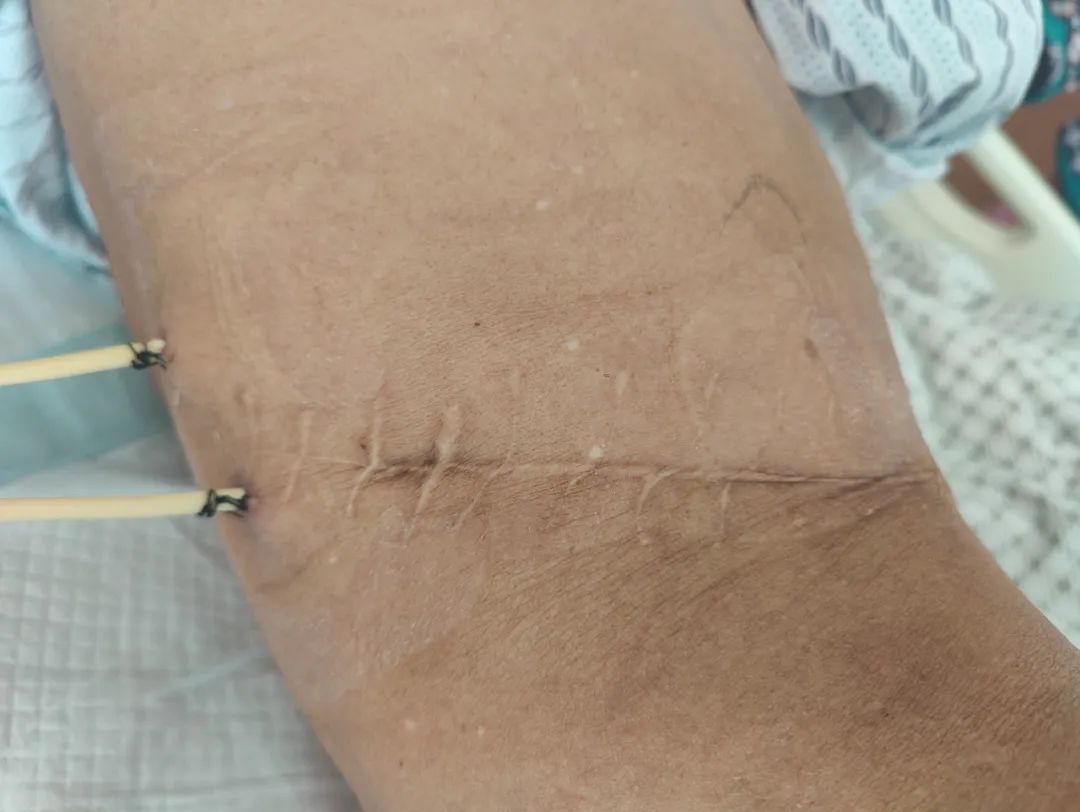

跨越28年的手术切口(20cm VS 两个0.8cm小孔)

于是老黄又回到了第二故乡台州,找到了恩泽医院泌尿外科主任医师王仙友。王仙友团队为老黄进行了全面的术前评估,在麻醉科和手术部的协助下,王仙友凭借丰富的经验和高超的手术技巧,采用双通道微创经皮肾镜钬激光碎石取石术,仅通过两个0.8厘米切口,成功击碎了1颗4.8厘米的铸形结石,同时取出1790颗豆状小结石。术后第二日老黄便开始下床活动。